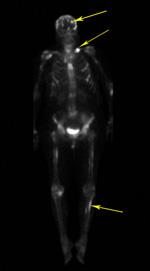

Bone scan

A technetium bone scan demonstrates extensive bony metastasis throughout the skeleton (arrows).